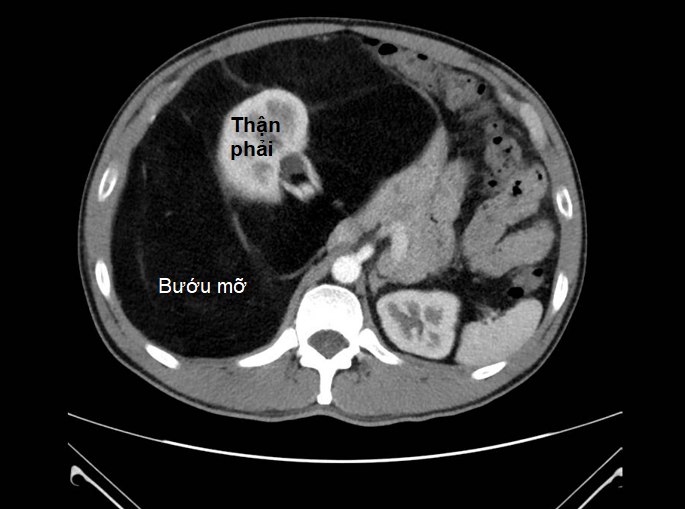

Bác sĩ Nguyễn Phúc Minh - trưởng khoa ngoại tiêu hóa Bệnh viện Bình Dân - cho biết kết quả chụp MRI bụng cho thấy khối bướu trong người anh T. có đường kính lên đến 40cm, cấu trúc tương đồng với mô mỡ, bao quanh thận phải.

Khối này dính và chèn ép các mạch máu lớn như động mạch, tĩnh mạch chủ bụng và các mạch máu lân cận làm suy giảm chức năng thận rất nghiêm trọng.

Tình trạng bướu mỡ choáng gần hết ổ bụng, chèn các mạch máu lớn và các mạch máu lân cận làm suy giảm chức năng thận của anh T. - Ảnh: BVCC